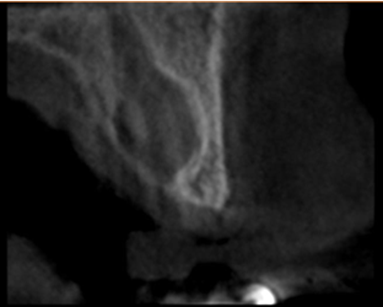

A well-defined unilocular radiolucent image in maxillary anterior region: Nasopalatine duct cyst (Figure 11).

Figure 11: Nasopalatine duct cyst.

Recurrence is rare, occurring in 0-11% of cases, according to reports. Following surgery, full reconstruction of the bones within the bony defect is expected (8). The intra-oral assessment showed diffuse non-tender isolated swelling in the anterior mid-palatal region (Figure 13). Radiographically, it presents as a well-defined oval or round radiolucency in the maxillary anterior tooth region (Figure 14).

Figure 14: Paraxial cut of the cyst.